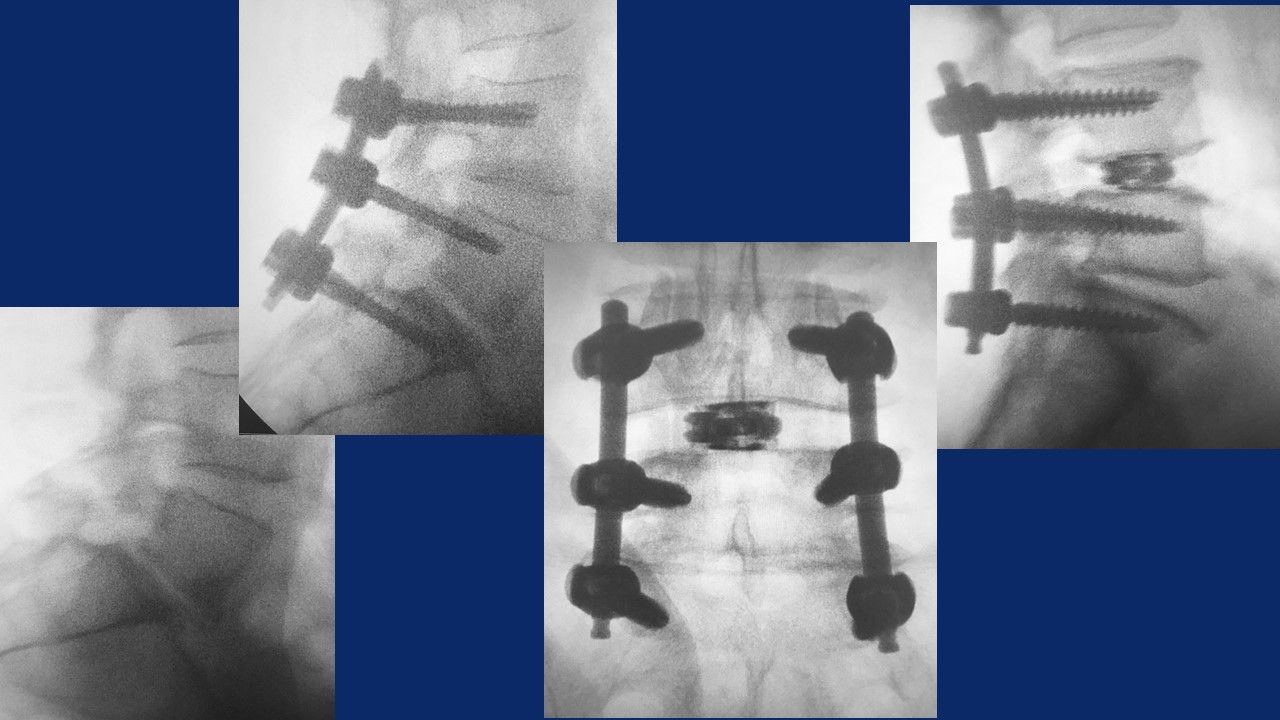

- nel trattamento delle instabilità del rachide (spondilolistesi congenite o degenerative) mediante interventi di stabilizzazione mininvasiva percutanea con barre e viti , barre e viti cementate, tlif, plif, xlif, artrodesi delle faccette articolari.

Stabilizzazione barre e viti percutanea

Artrodesi percutanea (tlif, plif, xlif)